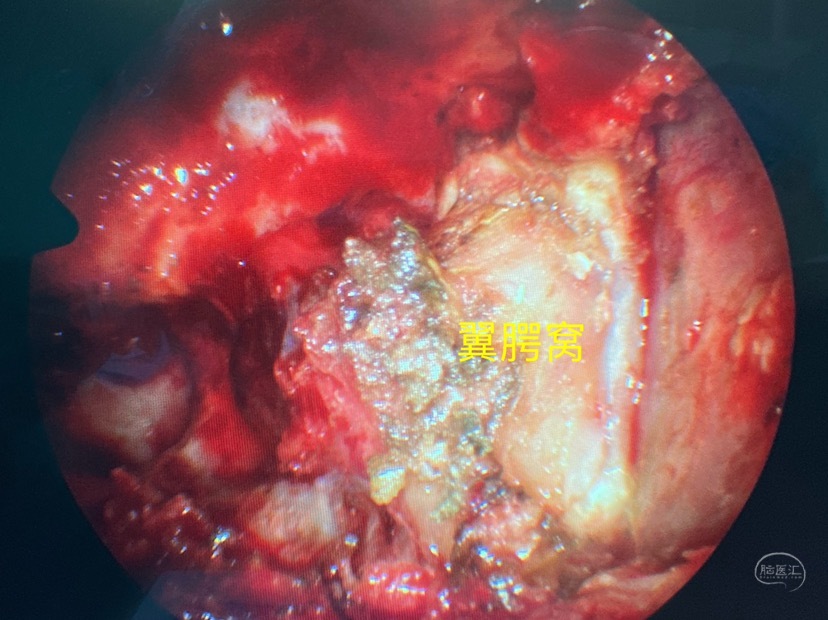

开放上颌窦后壁进入翼腭窝

将翼腭窝内容物移位显露翼突根部

磨开部分翼管骨质显露翼管神经,及其后方膨出的脑组织

磨除翼突根部充分显露外侧隐窝